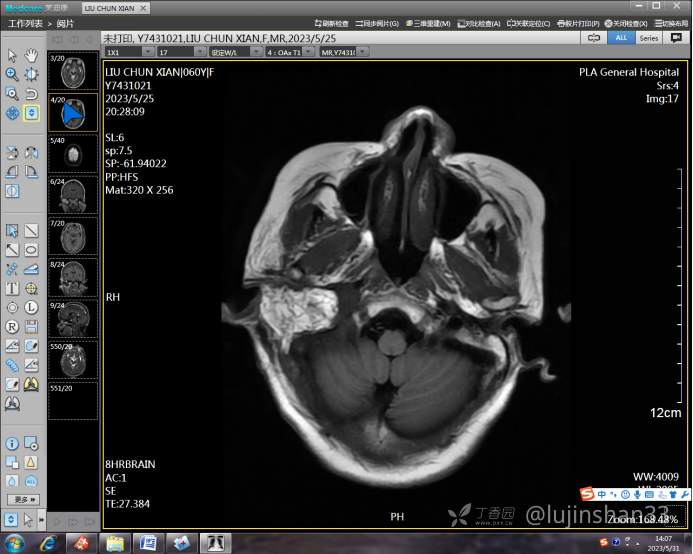

(2023-05-15 10:00,本院)行磁共振(颅脑)检查提示:右侧乳突区异常信号,考虑恶性、软骨来源肿瘤,软骨肉瘤可能性大。(集体讨论意见);脑内散在多发缺血灶。